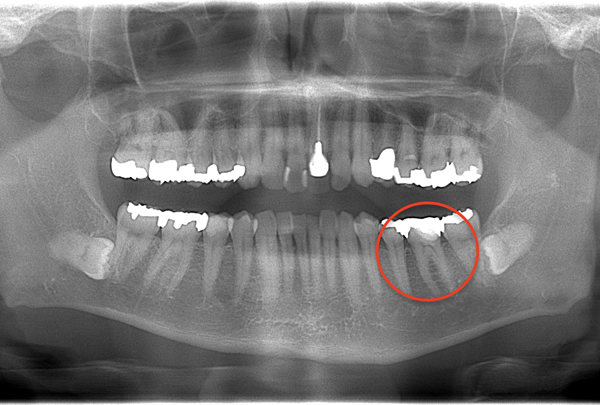

パノラマレントゲン写真

説明:

上顎左側臼歯部に残根があり周囲に透過像が見られる。また下顎右側臼歯部に根尖部から根分岐部に及ぶ透過像がある。また左右上下顎智歯には歯髄に達する透過像や歯冠周囲を覆う透過像が見られ歯周疾患が進行していることが取れる。

担当医師所見:

臼歯部に残根状態の歯牙があり、またカリエス(虫歯)の散在が認められる。残根部分の両隣在歯は欠損部に対して傾斜し始めている。